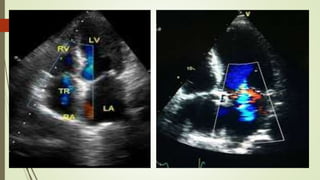

 Doppler Examination (AoV

Level):

Color Doppler :

AoV, PV, TV

Spectral Doppler :

 PW: PV (place sample volume in the

RVOT, 1 cm proximal to PV).

 CW: Place cursor through the vena

contracta of the TV or PV regurgitant jet,

or the valve leaflet coaptation point.